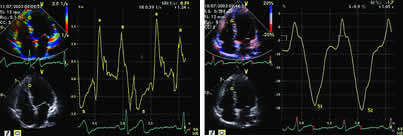

图1 正常人的心肌应变(左图)和应变率(右图)显像,正常的应变图像主要由收缩期负相波型组成,其最大值为St。正常的应变率图像由一个收缩期的负相波型s和两个舒张期正相波型e和a组成。